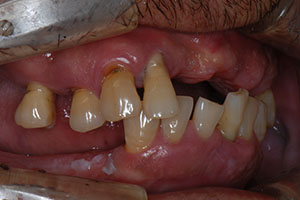

치료증례 전후사진

Before & After

a9db3067cff1c27c28aa713ee7f36abc_1698976199_9893.jpg